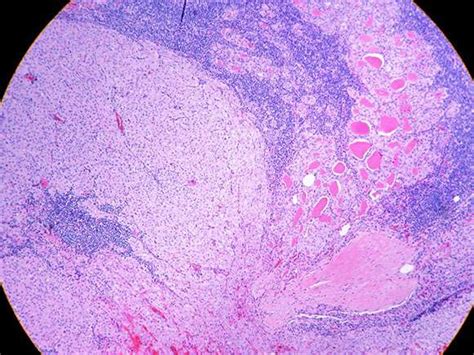

So, what is oncocytic variant papillary thyroid carcinoma , anyway? At its core, it’s a subtype of papillary thyroid cancer, which is the most common type of thyroid cancer. The ‘papillary’ part refers to the microscopic appearance of the cancer cells – they often form finger-like projections, kind of like papillae. The ‘oncocytic’ part is where things get a little more specific. It means the cancer cells have a distinctive feature under the microscope: they contain an abundance of oncocytes , which are cells packed with mitochondria . Mitochondria are the powerhouses of our cells, and in oncocytes, they’re supercharged, giving the cells a granular, eosinophilic (pinkish) appearance. This specific cellular makeup is what distinguishes this variant from other forms of papillary thyroid cancer. While it shares many characteristics with classic papillary thyroid cancer, including the potential for spread to lymph nodes, the oncocytic change can sometimes influence how the cancer behaves and how it responds to treatment. It’s crucial to remember that even though it’s a ‘variant,’ it’s still a form of cancer, and like all cancers, it requires careful management. The presence of oncocytes doesn’t automatically mean a worse prognosis, but it’s a key characteristic that pathologists look for to classify the tumor accurately. This accurate classification is vital because it helps doctors tailor the treatment plan to the individual patient. We’ll get more into the nitty-gritty of diagnosis and treatment later, but for now, just know that this variant is defined by the specific look of its cells under a microscope, due to an overabundance of mitochondria.

Let’s geek out for a sec about those mitochondria and oncocytes we just mentioned. In the world of oncocytic variant papillary thyroid carcinoma , these guys are the stars of the show, microscopically speaking. Mitochondria, as I said, are the energy factories of our cells. They take nutrients and oxygen and convert them into energy that our cells need to function. In oncocytes, these mitochondria are present in massive numbers, making the cell’s cytoplasm (the stuff inside the cell membrane but outside the nucleus) look granular and intensely pink when stained for examination. This accumulation of mitochondria is often associated with specific genetic changes and can influence the cell’s metabolism and behavior. It’s fascinating stuff, right? Think of it like a car engine that’s been super-tuned with way more cylinders and fuel injectors than usual – it’s running at a different capacity. This cellular characteristic is so pronounced that it’s the defining feature pathologists use to label this variant. While classic papillary thyroid carcinoma cells might have some mitochondria, oncocytes take it to a whole new level. This difference isn’t just a cosmetic detail for the microscope; it can have implications for how the cancer cells function and potentially how they respond to therapies. For example, some studies suggest that the metabolic state of these mitochondria-rich cells might influence their sensitivity to certain treatments. Understanding this cellular quirk is a big part of why accurate diagnosis is so important. It helps doctors make more informed decisions about the best course of action for each patient. So, while the term ‘oncocyte’ might sound technical, it’s simply a descriptor for a cell that’s brimming with these energy-producing organelles, giving it a unique appearance and potentially unique behaviors within the context of thyroid cancer. It’s a really cool example of how cellular biology plays a role in disease.